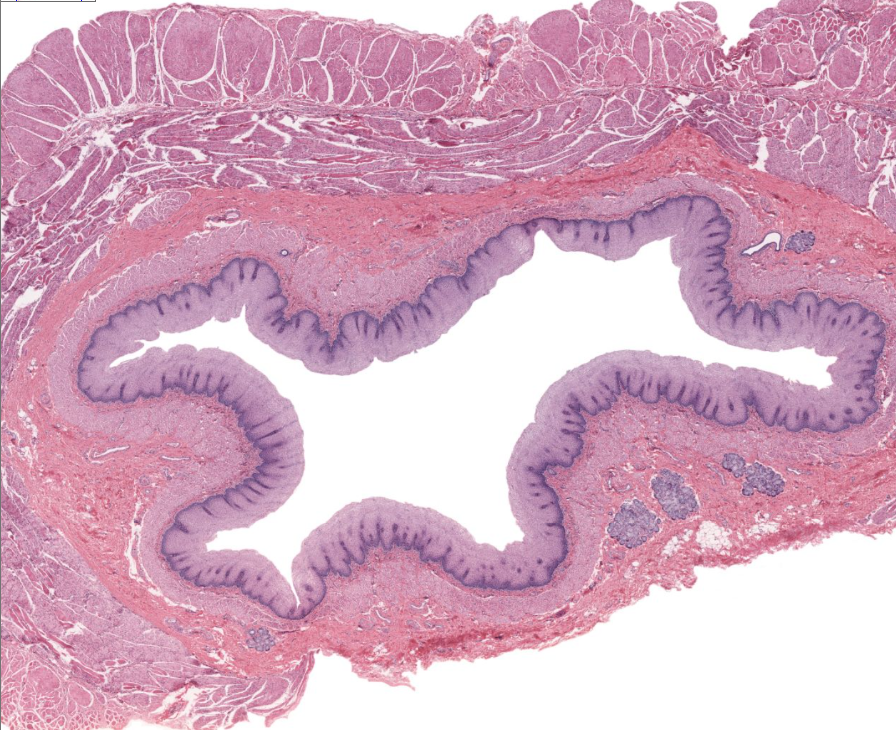

esophagus

note strat sq. epi